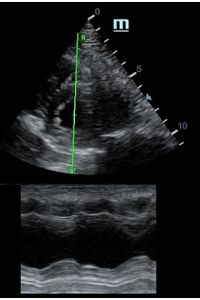

Оценка сокращения сегментов левого желудочка на глаз постепенно уходит в прошлое. Если в приборе нет функции радиального или лонгитудинального стрейна, на помощь опять может прийти Free Xros. Утолщение более 5 мм в систолу – нормальное сокращение, 2-5 мм гипокинез, истончение в систолу – дискинез.